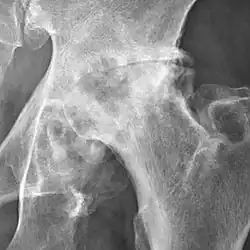

The most commonly used radiographic classification system for osteoarthritis of the hip joint is the Kellgren–Lawrence system (or KL system).[6] It uses plain radiographs.

Osteoarthritis of the hip joint may also be graded by Tönnis classification. There is no consensus whether it is more or less reliable than the Kellgren-Lawrence system.[8]

Severe (Tönnis grade 3) osteoarthritis of the hip.

severe joint space narrowing, or joint space obliteration

severe deformity of the head